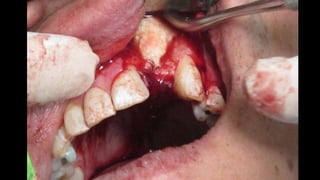

El documento trata sobre la cirugía bucal para plastía del proceso alveolar utilizando hueso humano y factores de crecimiento. También menciona los cuidados postoperatorios, que incluyen el uso de hielo, reposo, dieta líquida y antibióticos, evitando antiinflamatorios no esteroides. Se proporciona información adicional sobre las páginas web relacionadas con cirugía maxilofacial.